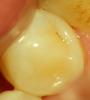

METT Опубликовано 18 апреля, 2013 Автор Поделиться Опубликовано 18 апреля, 2013 46-п-д-к 1-2 кл мед,глубокий,на дно SDR,обточка под вкладку Ссылка на комментарий

METT Опубликовано 20 апреля, 2013 Автор Поделиться Опубликовано 20 апреля, 2013 46-п-д-к 1-2 кл мед,глубокий,на дно SDR,обточка под вкладку 1 Ссылка на комментарий